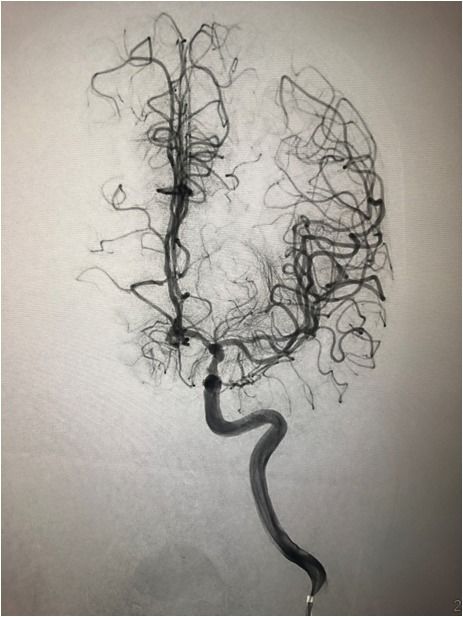

入院后75min,股动脉穿刺成功,后循环造影及右侧颈内动脉正侧位。

导丝导管通过闭塞部位,经微导管造影,证实在远端真腔内,取栓后M1重度狭窄,球囊扩张。

球囊扩张

支架植入术后前向血流通畅